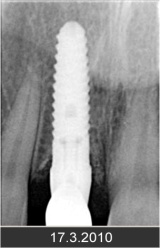

• Zavedení implantátu do kosti čelisti

• Zahojení do kosti – 3-4měsíce(v některých případech i déle – doplňování kosti)

Klasickým příkladem a indikací pro použití implantátu je ztráta jednoho zubu (v tomto případě v předním – frontálním úseku) v jinak zdravém, nepoškozeném chrupu.

Nejčastější příčinou takové ztráty je sportovní nebo dopravní úraz.

Náhrada jednoho zubu pomocí implantátu je možná také v postranním úseku chrupu. Při ztrátě většího počtu zubů ve frontálním nebo postranním úseku může být mezer uzavřena větším počtem jednotlivých implantátů.

Při ošetření pomocí jednotlivých implantátů zůstávají sousední zuby neporušené – intaktní. Při klasickém ošetření pomocí můstků musejí být tyto zuby obroušeny!